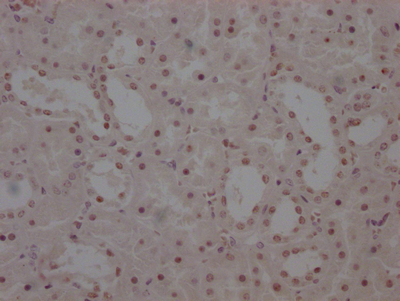

The image on the left is immunohistochemistry of paraffin-embedded Human gastic cancer tissue using CSB-PA051152(CYP2D6 Antibody) at dilution 1/30, on the right is treated with synthetic peptide. (Original magnification: ×200)

The image on the left is immunohistochemistry of paraffin-embedded Human thyroid cancer tissue using CSB-PA051152(CYP2D6 Antibody) at dilution 1/30, on the right is treated with synthetic peptide. (Original magnification: ×200)